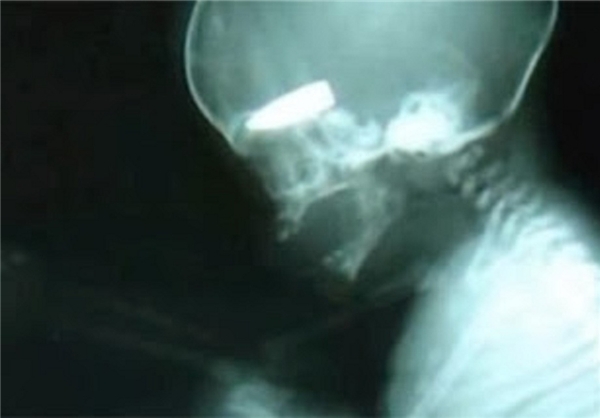

روزنامه دیلی میل انگلیس تصویری از کم سن و سال ترین قربانی خشونت‌های سوریه را منتشر کرد که قبل از باز کردن چشم‌هایش به این دنیا سرب داغ بر پیشانی‌اش نشست.

این تصویر متعلق به تصویر سونوگرافی یکی از زنان حامله سوری بود که اخیرا به دست تروریست‌های سوری از ناحیه شکم هدف اصابت گلوله قرار گرفته است، گلوله به سر جنین اصابت کرده و در عکس سونوگرافی کاملا مشهود است.

این زن بلافاصله بعد از اصابت گلوله به بیمارستان حلب منتقل شد تا با عمل جراحی جنین از شکم وی خارج شود، اما طبعا جنینی که گلوله وارد سرش شده، از بین رفته بود تا نام وی رکورددار کم سن و سال ترین قربانی جنایات تروریست های تکفیری در سوریه شود.